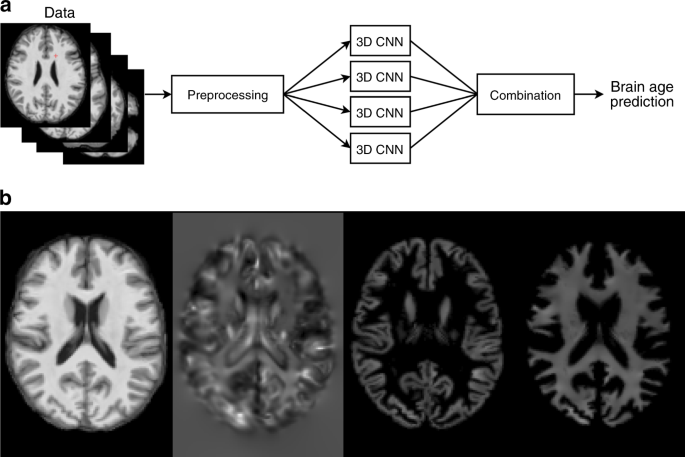

Here we present a new brain age prediction method (Fig. 1) that uses a 3D CNN trained on MRIs to predict brain age. The input data are a T1-weighted image registered to Montréal Neurological Institute (MNI) space and data derived from the T1-weighted image, i.e., a Jacobian map, and gray and white matter segmented images (Fig. 1). The input data also include information about the subject’s sex and the type of MRI scanner. The output of the network is the predicted brain age.

Illustration of the proposed method and input data. a A flowchart showing a high-level overview of the proposed brain age prediction system. b Examples of image types generated by the preprocessing step. From left to right: a registered T1-weighted slice, a Jacobian map slice, a GM segmented slice, and a WM segmented slice.

There are three types of images that the preprocessing step generates. The first is an MNI-registered image. Second, a Jacobian map which is a by-product of the deformable registration. Last, a gray matter and white matter soft segmented image. All of the image types mentioned above have voxel size 1.5 mm\({}^{3}\) and voxel resolution 121 × 145 × 121.